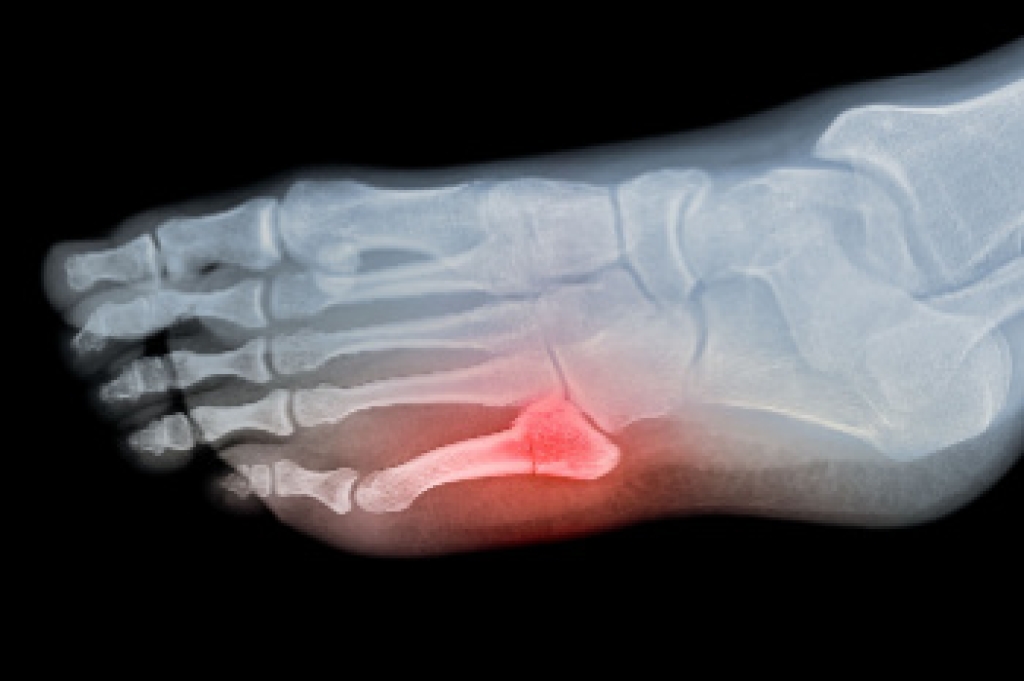

To figure out the cause of foot pain, podiatrists utilize several different methods. This can range from simple visual inspections and sensation tests to X-rays and MRI scans. Prior medical history, family medical history, and any recent physical traumatic events will all be taken into consideration for a proper diagnosis.

The Proper Healing of a Broken Ankle

Proper healing of a broken ankle requires timely medical attention, effective treatment, and careful rehabilitation. Treatment depends on the severity of the fracture. For minor fractures, non-surgical options like casting or using a walking boot may be sufficient to immobilize the ankle, allowing the bone to heal. More severe fractures, where the bone is misaligned or displaced, often require surgery using screws or plates to stabilize the bone. During recovery, rest and elevating the ankle can help to reduce swelling. Using crutches or a walker prevents putting weight on the ankle until cleared by a doctor. Targeted exercises play a critical role in regaining strength, mobility, and balance after the bone heals. Full recovery can take several weeks to months, depending on the injury's severity. If you have broken your ankle, it is strongly suggested that you visit a podiatrist as quickly as possible for a proper diagnosis and medical advice.

A broken ankle is experienced when a person fractures their tibia or fibula in the lower leg and ankle area. Both of these bones are attached at the bottom of the leg and combine to form what we know to be our ankle.

When a physician is referring to a break of the ankle, he or she is usually referring to a break in the area where the tibia and fibula are joined to create our ankle joint. Ankles are more prone to fractures because the ankle is an area that suffers a lot of pressure and stress. There are some obvious signs when a person experiences a fractured ankle, and the following symptoms may be present.